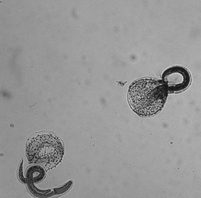

鶏回虫のライフサイクル:鶏回虫は、感染した宿主の糞の中で排出される虫卵の摂取によってニワトリに伝播されます。

ニワトリが虫卵を摂取すると、虫卵はニワトリの消化管の前胃または十二指腸で孵化します。孵化したばかりの線虫が成虫になるには28~30日かかり、感染後の潜伏期間は5~8週間(鳥が糞の中に虫卵を排出し始める)です。

環境中での生存:温度と湿度の最適条件下で、鶏回虫卵は環境中で8か月間生存でき、7~28日で糞便を通過した後に感染性となります。卵は低温 (凍結しない) に耐性がありますが、直射日光や乾燥にさらされると死滅します。